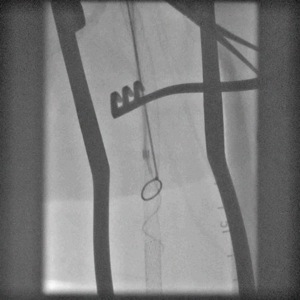

When conduit is limited, or PTFE or cadaver vein is being considered, in the setting of occluded SFA stents, I have found that it is possible and perhaps preferable to attempt removal of these stents using remote endarterectomy.

The additional material needed is fluoroscopy and endovascular skills. Directing a subintimal Glidewire helps free the stent and aid passage of the Moll ring dissector.

Adding cold saline seems to help shrink the stents. A plaque free distal end point allow the stents to be removed with a gentle tug.

I put these patients on coumadin anticoagulation. Surveillance is needed for recurrent stenoses -typically these occur randomly as focal TASC A stenoses, and likely represent remnant medial tissues that have caused intimal hyperplasia. This may be particularly amenable to treatment with drug eluting balloons. Failure as thrombosis typically is limited to the treated vessel without the embolism seen when PTFE grafts fail. Failure tends to occur in smokers. Inability to pass the dissector is usually seen in patients with heavy calcification -diabetics, renal failure, and I would avoid attempting remote endarterectomy in these patients. When the dissectors fail to pass, cutting down and directly endarterectomizing the vessel and resuming remote endarterectomy is feasible. The common femoral artery is repaired with a patch. I try to avoid having to place a distal stent and when a tapered end point, as in a successful carotid endarterectomy, is achieved, usually unnecessary.